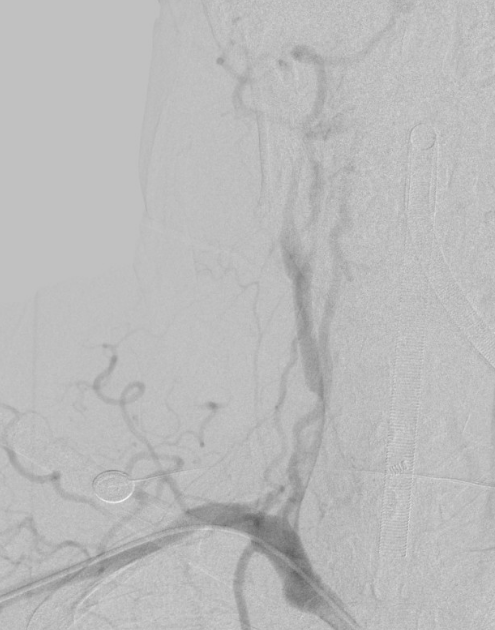

第一步,脑血管科团队马上为患者行“脑血管造影+颈动脉支架置入术”。第一步的枢纽难点在于:传统经股动脉入路时,导丝在主动脉夹层内难以准确参加主动脉真腔,操气派险高、胜仗率低。经多学科团队充分评估商议后,脑血管科改革性遴荐经肱动脉入路,经锁骨下动脉参加主动脉,在导丝交流下得手参加真腔。

在此基础上,进一步卓越长节段夹层,精确参加右侧颈总动脉真腔,植入支架建造血管内膜扯破,胜仗复原脑部血流,昭彰改善脑低灌输景况,为后续主动脉夹层外科手术创造了安全条目,获取了可贵的时代窗口,也为患者神经功能的复原奠定了基础。

△右颈总动脉术前术后对比